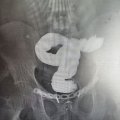

В хирургическое отделение Каширской ЦРБ после распития различных алкогольных напитков в большом количестве поступил 24-летний Николай (имя изменено). В результате изрядного употребления спиртного у него развился тяжелый панкреатит с клинической картиной, который требовал немедленного вмешательства. Как сообщили в ЦРБ, пациенту провели консервативную терапию, однако она не принесла ожидаемых результатов. Симптомы интоксикации усиливались, а боль в животе становилась нестерпимой. Врачи приняли решение о проведении операции – лапароскопического дренирования сальниковой сумки и брюшной полости.

«Во время операции выяснилось, что у пациента развился тяжелый деструктивный панкреатит с формированием парапанкреатического инфильтрата. В брюшной полости определялось большое количество серозно-геморрагического экссудата – ферментативный перитонит. Командой хирургов операция была выполнена успешно, – рассказал заведующий хирургическим отделением Каширской ЦРБ Александр Страчук.

По его словам, дренирование через небольшие проколы позволило удалить экссудат и обеспечить нормальное отток жидкости из сальниковой сумки и брюшной полости. Благодаря миниинвазивной технологии удалось избежать объемного травматичного вмешательства, после которого у пациента было бы длительное заживление ран и тяжелая реабилитация в послеоперационном периоде. Сейчас Николай находится на пути к выздоровлению. Врачи отмечают, что благодаря своей молодости и силе воли, он сможет полностью восстановиться и вернуться к обычной жизни.